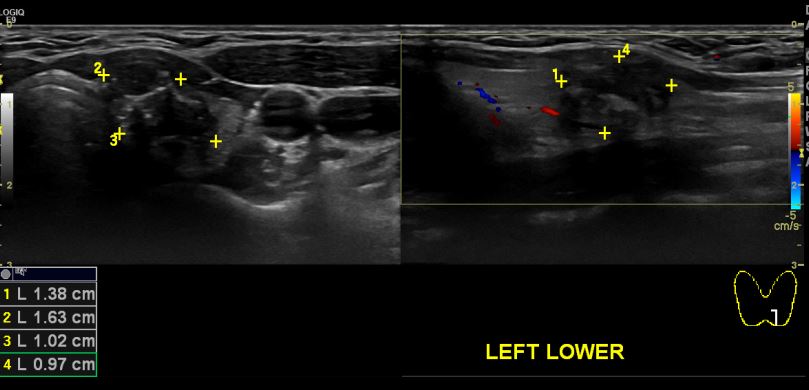

오래전부터 좌측목에 만져지는 멍울 있어 검진위해 내원하신 34세 여자환자분으로

좌측갑상선 세포흡인병리검사 실시한후 유두암진단되셨습니다.